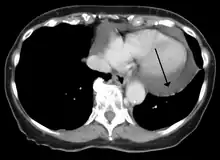

Cardiac CT and MRI scans: cross-sectional imaging with computed tomography (CT) can help localize and quantify the effusion, especially in a loculated effusion (an effusion contained to one area).[12] CT imaging also helps assess for pericardial pathology (pericardial thickening, constrictive pericarditis, malignancy-associated pericarditis).[1] Whereas cardiac MRI is reserved for patients with poor echocardiogram findings and for assessing pericardial inflammation, especially for patients with continued inflammation despite treatment.[5] CT and MRI imaging can also be used for continued follow up on patients.

A CT scan showing a pericardial effusion

A CT scan showing a pericardial effusion A large anechoic (black) pericardial effusion as seen on ultrasound. Closed arrow: the heart, open arrow: the effusion